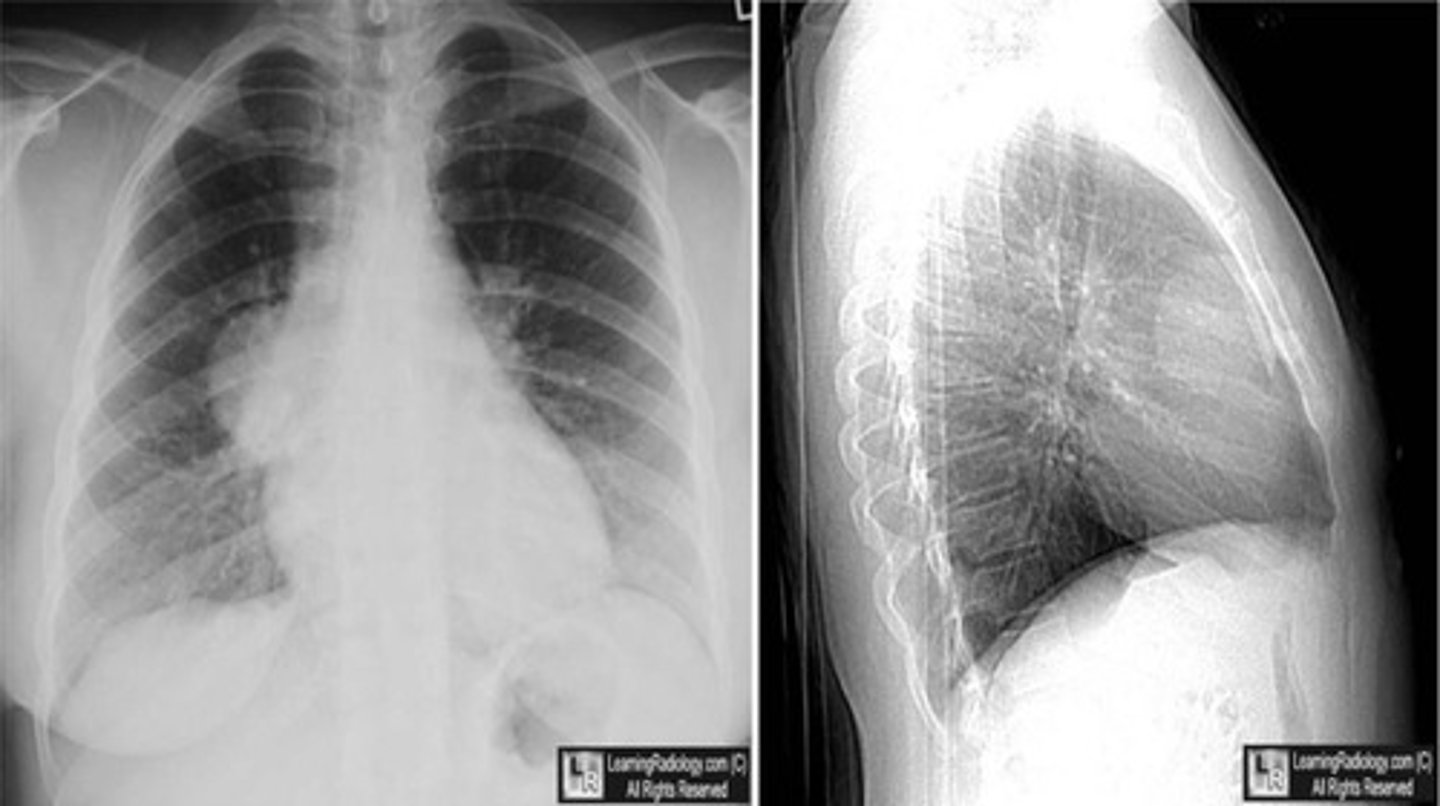

-posteroanterior view -goes from back to front

PA view

Lateral view